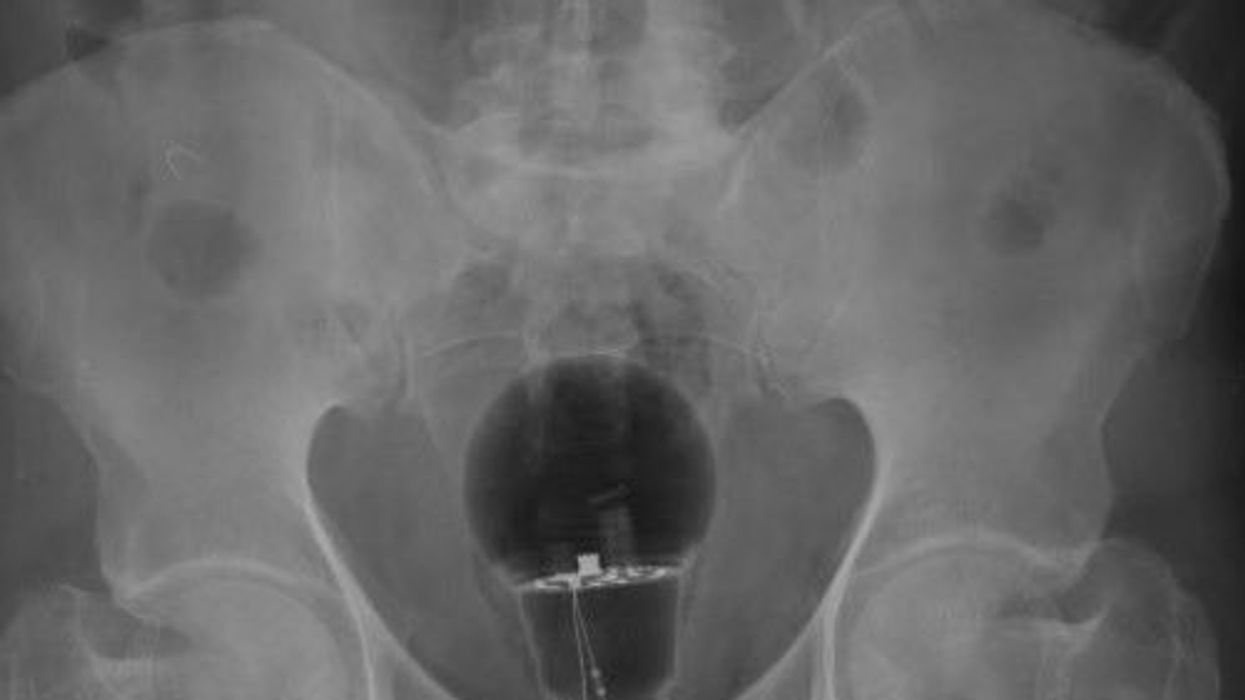

A patient in pain went to the hospital and left doctors stunned when an X-ray showed a lightbulb up his bottom.

Dr Julian Pylori, a gastroenterologist, said the foreign object was not spotted in a normal rectal examination.

But the doctor, who treats digestive disorders, was stunned when the bulb showed up on the X-ray.

Dr Pylori said: “Not palpable on rectal examination.

“Foreign body material, unknown.

“Endoscopic removal?”